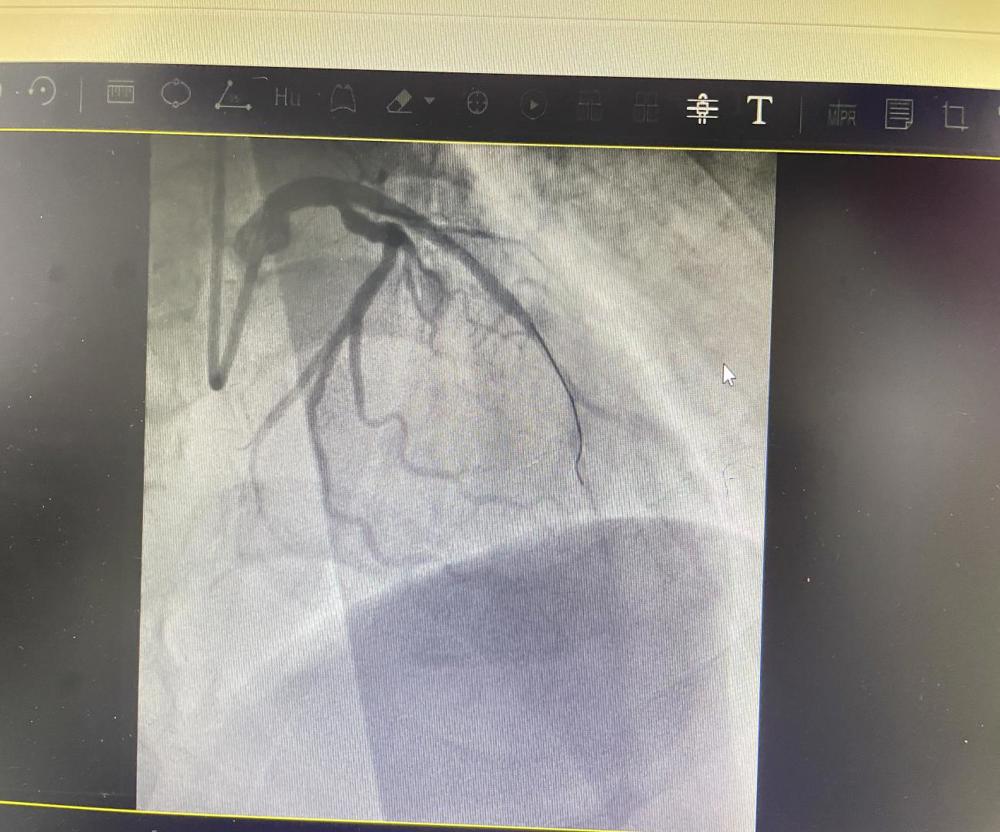

术前准备时,范叔突发室速、室颤、呼吸停止,急诊科团队临危不乱,对其给予电复律、电除颤、心肺复苏等进行抢救。范叔恢复心率后,心内科介入团队立即经右桡动脉行冠脉造影结果示:前降支近段急性闭塞,予行前降支PTCA+血栓抽吸+支架置入术。术后患者恢复自主意识,胸痛症状缓解,但是生命体征不稳定,转入ICU 进一步治疗。

未开通血管前

开通血管后